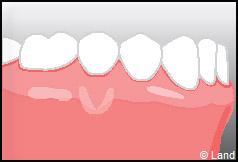

Les conséquences de cette mise à nu de la racine dentaire sont multiples, le patient peut présenter une hypersensibilité dentaire et l’aspect de ces récessions peut être inesthétique. Dans ce cas, la chirurgie muco-gingivale est recommandée et elle peut se faire de différentes façons.

Aussi, pour corriger ces défauts, on fait appel à la chirurgie muco-gingivale.